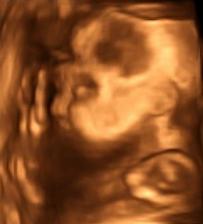

naše miminko je zatím úplně malinké, ale stejně už se koukám po věcičkách, které se mi líbí a které budou třeba 🙂

ten čas nám začal nějak hrozně utíkat, začíná mě děsit, že za tři měsíce by se měla naše malá princeznička narodit a já nemám pořádně ještě nic nachystáno ☹ takže se do toho začínám vrhat po hlavě, abych to všechno stihla připravit... držte mi palce 🙂

pátek třináctého jak vyšitý, po kontrole u doktorky jsem začala slabě krvácet, takže ležim v nemocnici, ale princezna je v pořádku a to je důležitý